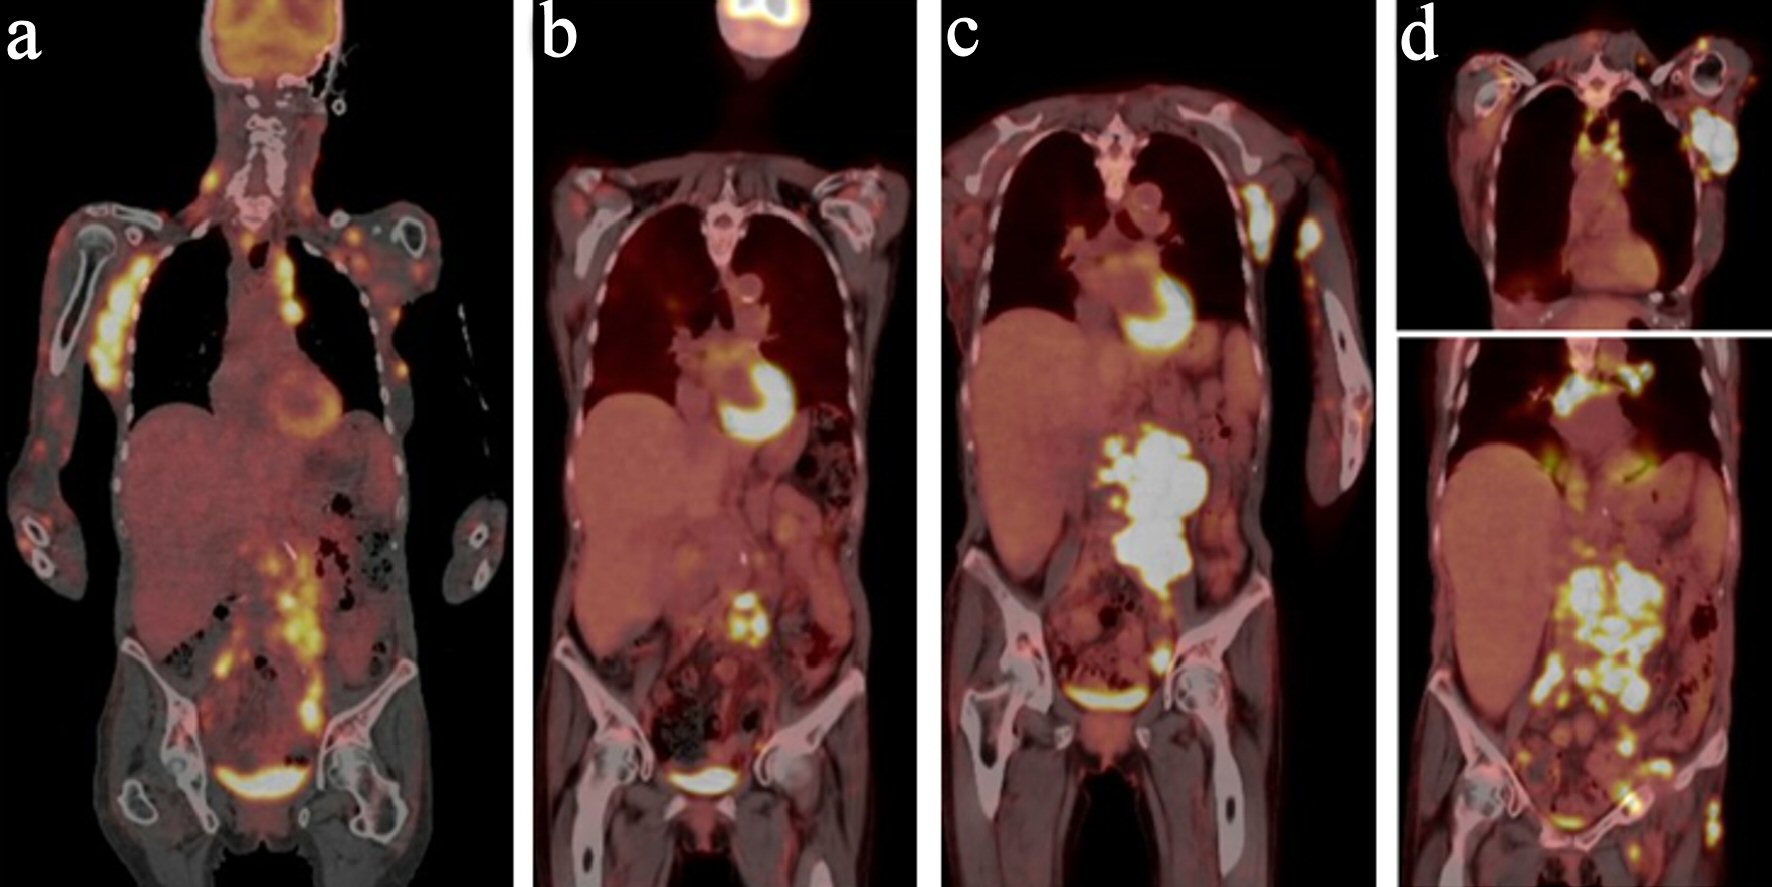

A 73-year-old female with a past medical history of eosinophilic fasciitis, presented with left axillary and left inguinal lymphadenopathy that was biopsied showing ill-defined nodular and diffuse aggregates (cluster of differentiation (CD)3+, CD4+, CD10+, PD1+, and CD30 with 10% partial expression) admixed with larger immunoblasts and prominent blood vessels, consistent with AITL. The patient was referred to our center from outside facility; we could not obtain a picture of the pathology at initial diagnosis. The patient initially opted for a trial of alternative therapy but re-presented 7 months later with extensive cutaneous disease in her arms, face, neck, and anterior chest, worsening lymphadenopathy (Fig. 1a) and fatigue. She still did not want to start conventional chemotherapy, so she was initiated on the anti-CD30 antibody drug conjugate, brentuximab, along with palliative radiation for symptomatic management. In spite of initial near clearance of all her skin lesions and most of her lymphadenopathy on brentuximab (Fig. 1b), after nine doses over 7 months, subsequent positron emission tomography-computed tomography (PET-CT) showed evidence of progression with worsening lymphadenopathy (Fig. 1c). The patient refused to have a repeated biopsy and after tumor board discussion, the patient was then started on mogamulizumab, with resolution of her skin lesions and cervical lymphadenopathy. However, repeat PET-CT after 10 doses of the mogamulizumab, showed mixed response but with the development of new hypermetabolic lymph nodes consistent with progression of disease (Fig. 1d), so the patient was referred for a clinical trial. However, prior to the first course of the trial treatment, a repeat lymph node biopsy of the left axillary lymph node showed evidence of EBV + DLBCL, without definitive evidence of her previous AITL (Fig. 2). Given the new pathology findings, the patient was started on bendamustine with rituximab, with the anti-CD79a monoclonal antibody, polatuzumab.

![]() Click for large image | Figure 1. PET-CT panel with initial PET-CT, PET-CT with progression in February, 2019, PET-CT in May, 2019 and PET in July, 2019. (a) PET-CT at initial diagnosis. (b) PET-CT after brentuximab. (c) PET-CT with progression on brentuximab. (d) PET-CT with progression on mogamulizumab. PET-CT: positron emission tomography-computed tomography. |